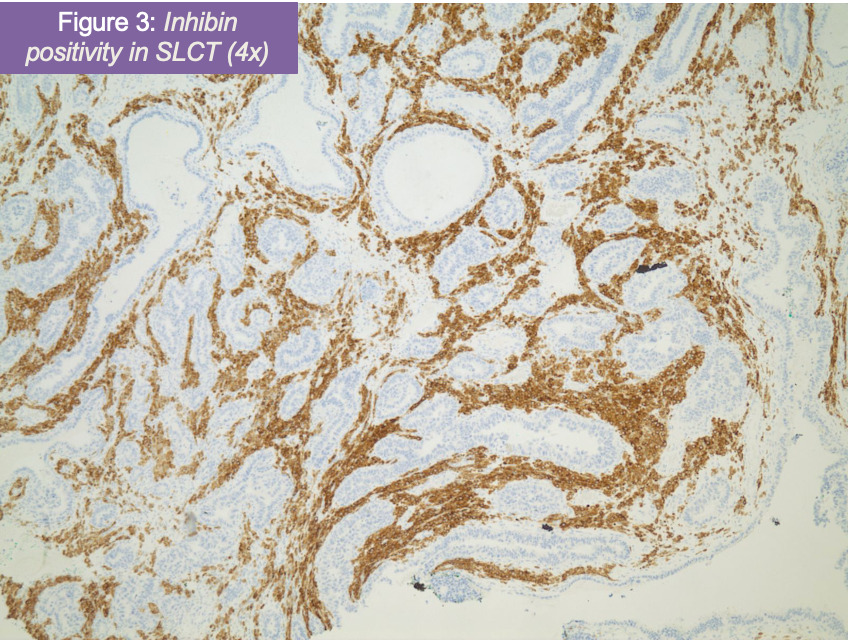

Pathologic review confirmed a poorly differentiated Sertoli-Leydig cell tumor (figure 1) of the right ovary (Stage IIIIC- pT3C Nx M0) with metastasis to the omentum and right pelvic side wall. Additionally, the right ovary was positive for high grade serous carcinoma (figure 2) metastatic from the fallopian tube. After H&E examination, immunostains for p53, napsin, PAX8, synaptophysin, CD56, and inhibin were ordered with adequate controls. Tumor cells corresponding to poorly differentiated Sertoli-Leydig tumor were positive for p53 (patchy), CD56, and inhibin (figure 3), while negative for PAX8, napsin, and synaptophysin. The metastatic high grade serous carcinoma was only positive for PAX8 and p53 (diffuse).